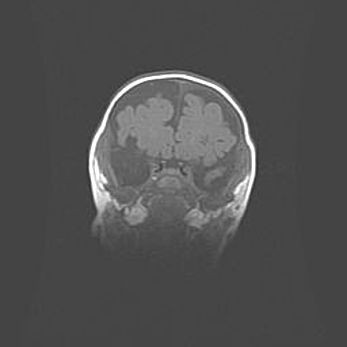

Множественные кисты обоих полушарий головного мозга, наибольшая из них в правой затылочной области. Ассиметричная атрофическая гидроцефалия.

Возраст: 7 месяцев

Вес: 5660 г

Пол: мужской

Окружность головы: 41,5 см

Срок гестации: 28-29 недель

Кисты головного мозга развиваются в результате многоочаговых некрозов вещества мозга и возникают вследствие перенесенной перинатальной инфекции, менингитов, энцефалитов, асфиксии, родовой травмы, расстройств мозгового кровообращения различного генеза. Образованию кист в веществе головного мозга плодов и новорожденных способствуют такие факторы, как высокое содержание в нем воды, недостаточная (или отсутствие) миелинизация и слабая астроглиальная реакция на повреждение.

Кисты могут сочетаться с гидроцефалией и другими поражениями головного мозга.